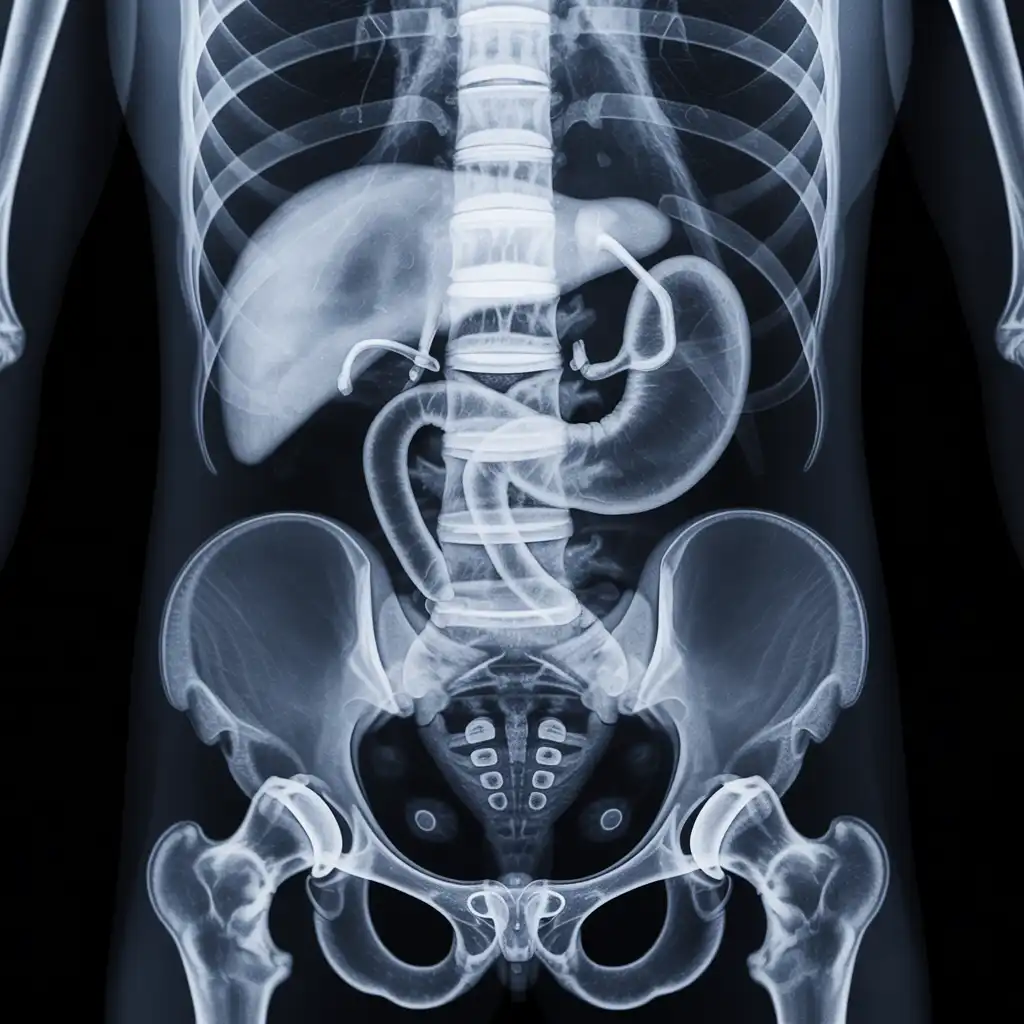

Una radiografia a domicilio è un esame radiologico eseguito da un tecnico specializzato che viene a casa tua con apparecchiature digitali portatili. L’esame si svolge sul posto, senza spostare il paziente e con la stessa qualità di una struttura ospedaliera.

Dopo l’acquisizione delle immagini, queste vengono inviate al medico radiologo che referta rapidamente e ti invia tutto in formato digitale. Un servizio comodo, sicuro e ideale per chi ha difficoltà negli spostamenti.

Siamo un team di tecnici radiologi qualificati con anni di esperienza maturata in strutture sanitarie di Pescara e provincia. Abbiamo scelto di portare la diagnostica direttamente nelle case dei pazienti, offrendo radiografie a domicilio con la stessa precisione degli esami eseguiti in ambulatorio, ma con tutta la comodità del proprio ambiente. Nel tempo abbiamo eseguito migliaia di esami a domicilio in abitazioni private, residenze per anziani e centri assistenziali, utilizzando apparecchiature digitali portatili certificate e procedure rapide, sicure e adatte anche ai pazienti con difficoltà di movimento. Con Radidom Pescara mettiamo al centro la persona: competenza, cura e tecnologia al servizio della tua salute, ovunque tu sia.